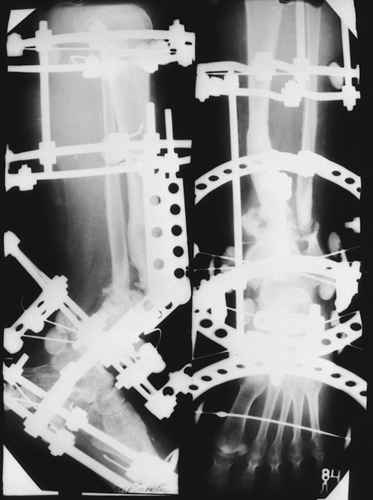

На первом этапе аппаратом Илизарова закрыто устранена деформация голени.

На втором этапе произведёно освежение краёв костных фрагментов б/б и м/б костей с приданием проксимальному фрагменту б/б кости впалой, а дистальному выпуклой формы, открытие канала проксимального фрагмента и погружной остеосинтез, а также остеотомия б/б кости в в/3 и м/б кости на границе с/3 и н/3 голени. Больной проводился одновременный бифокальный компрессионно-дистракционный остеосинтез. Достигнуто 11 см. удлинение и сращение ВПГ.

Срок лечения 11 месяцев. Наблюдение 2 года.